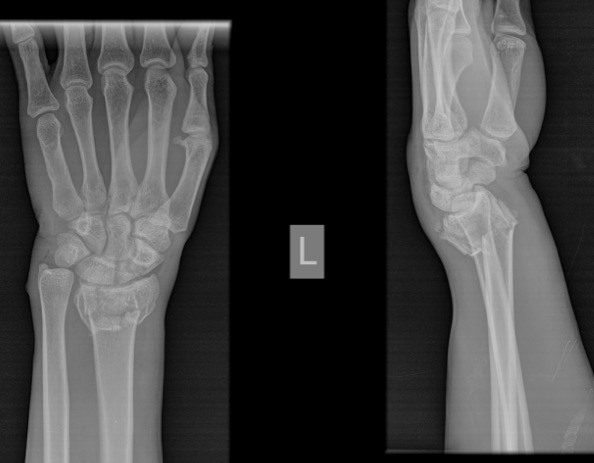

31岁的卡拉狄(音译)是一名汽修工,下雨天的时候搬运轮胎不小心踩到青苔滑倒,手着地的时候刚好崴到了腕关节,拍了片子,显示桡骨远端骨折(Colles骨折),端断分离移位。当地的医生当下给他做了复位处理,打了石膏,但是卡拉狄的疼痛并没有就此消失,反而更加厉害。住几十公里以外的卡拉狄听说中国骨科医生到莱索托了,于是驱车来到医疗队寻求帮助。

患者CT。

卡拉狄到达的时候已是半夜12时,王冠清接到通知一直在等着他的到来。卡拉狄的CT片以及腕部状况显示他的骨折并没有复位,且一直处于畸形状态。“Colles骨折多为间接*力暴**所引起,常见于跌倒,肘部伸展,前臂旋前,腕关节背伸,手掌着地致伤。应力作用于桡骨远端,使得这一脆弱部分发生骨折。”王冠清在询问卡拉狄的意见后决定为他实施中医正骨手法解决他的腕部问题。